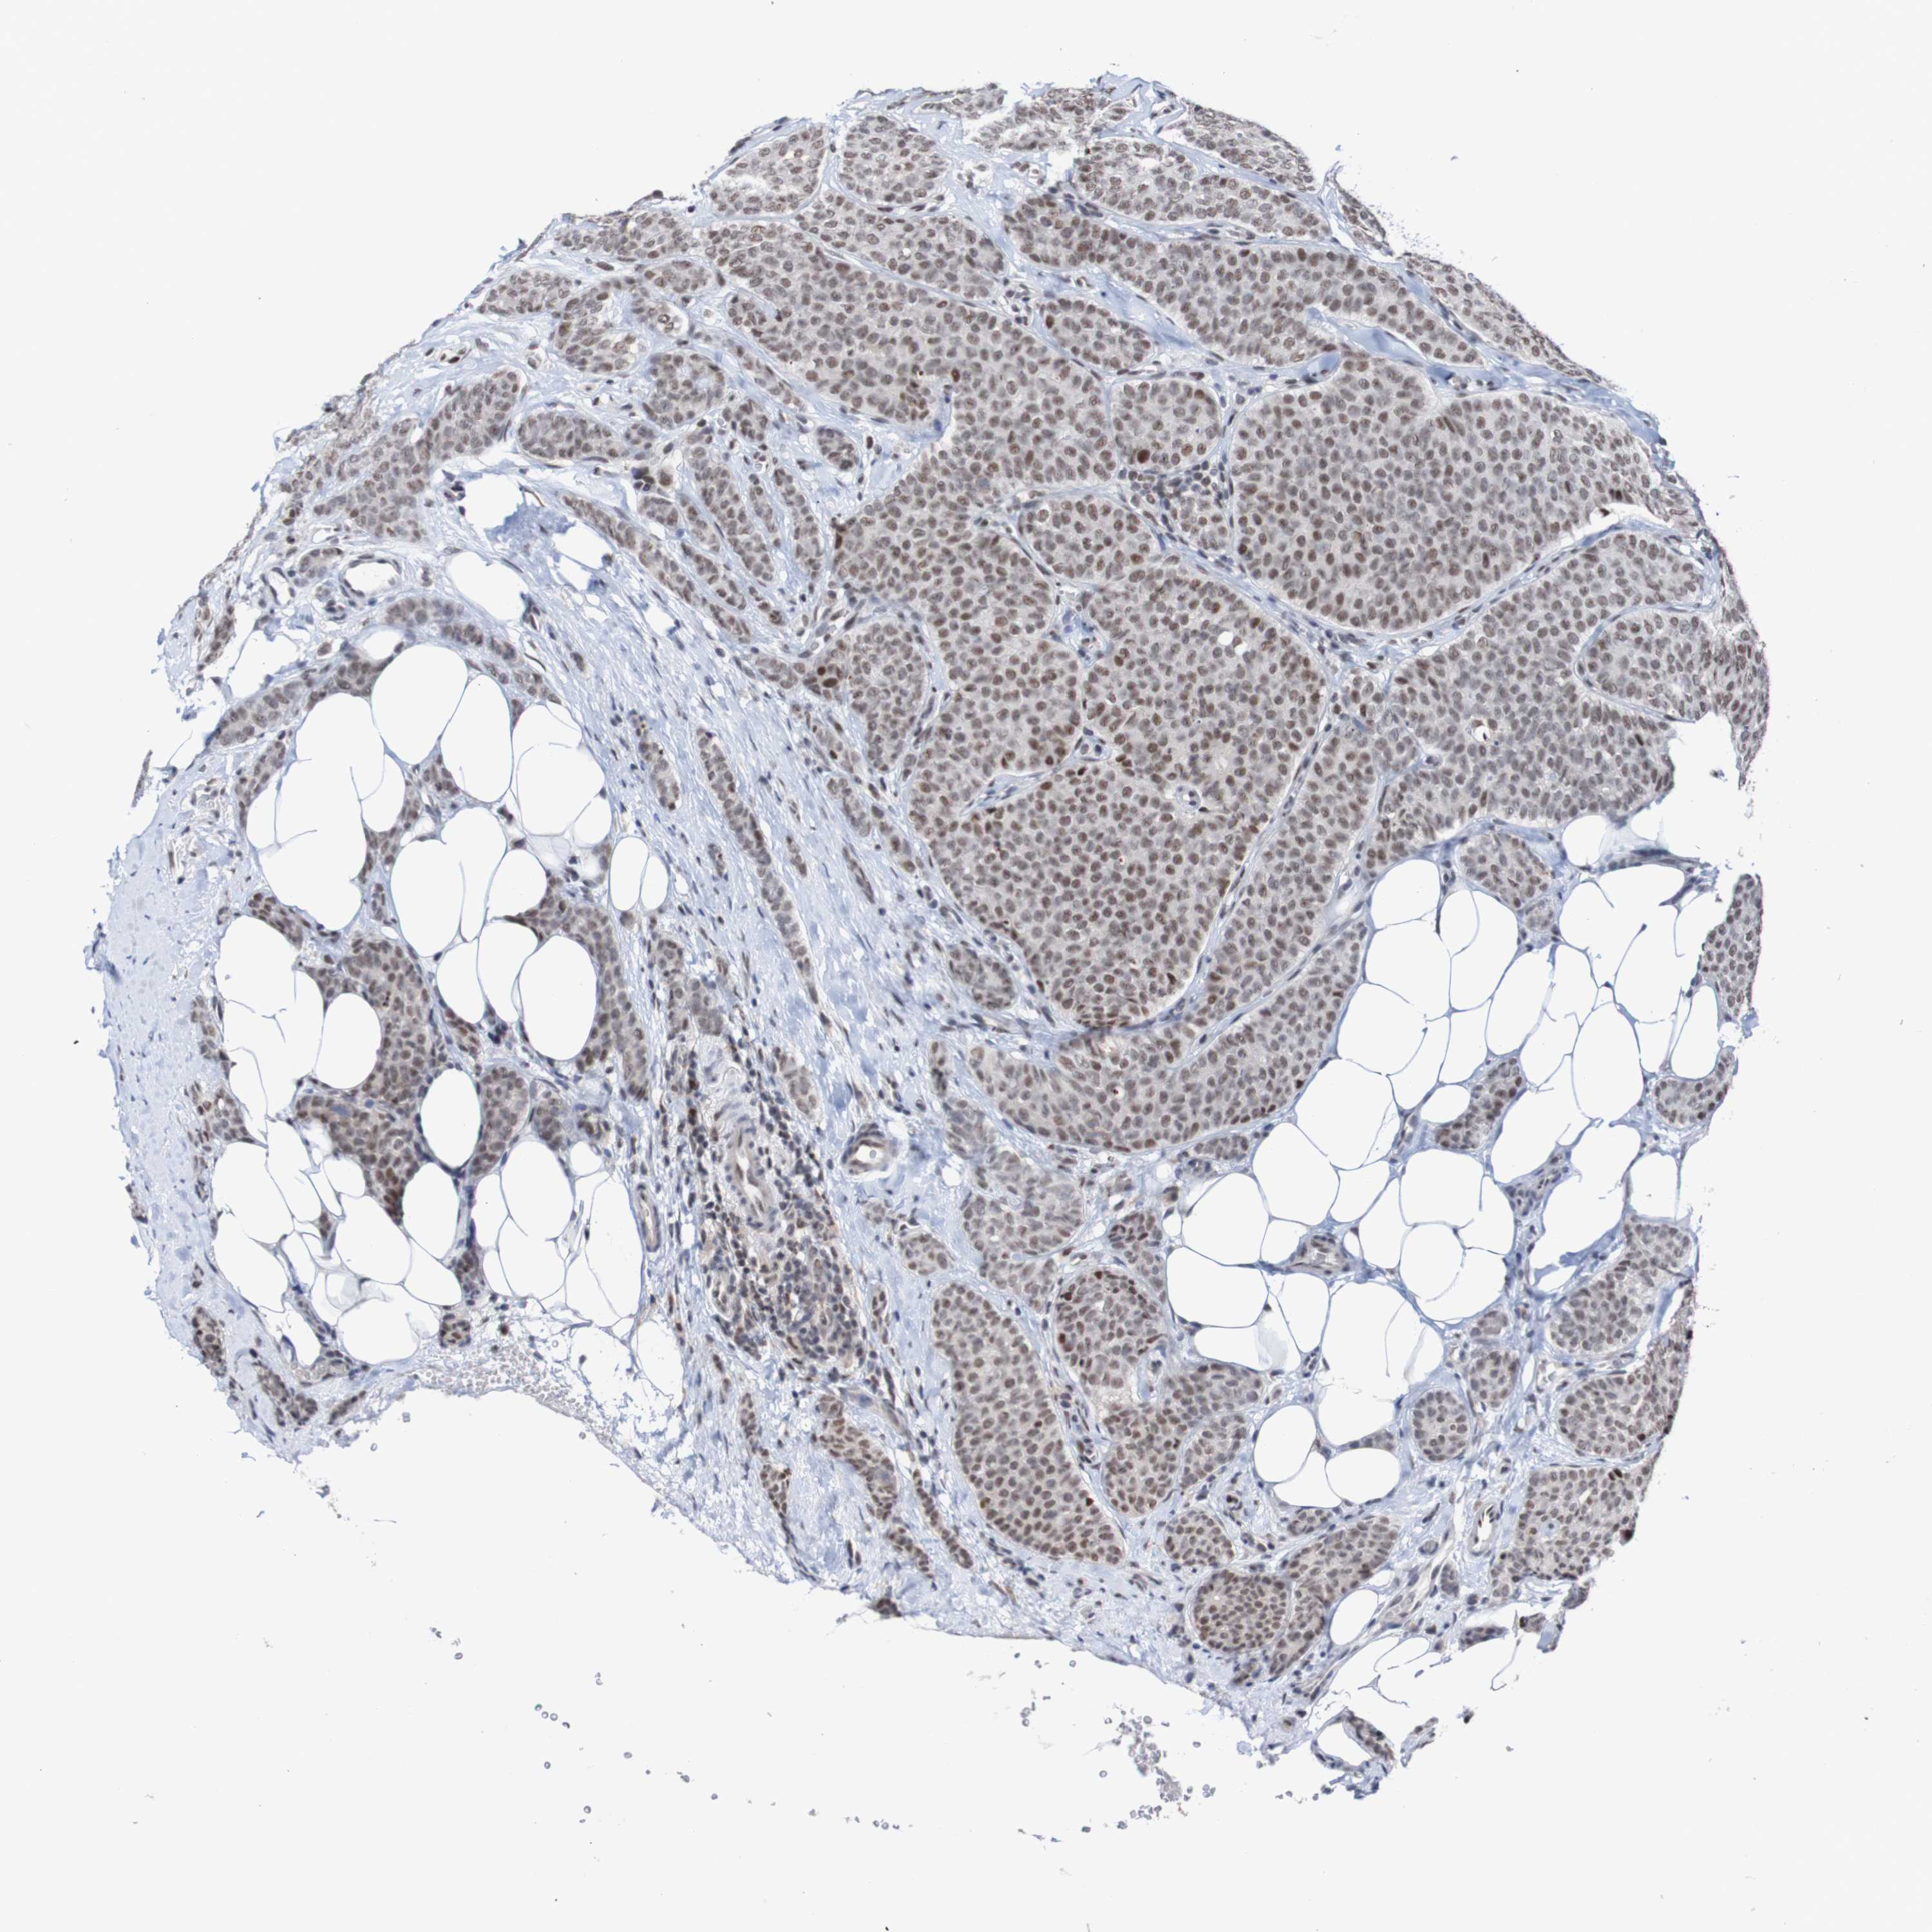

CANCER BREAST CANCER Show tissue menu

BRCA TCGA BRCA VALIDATION PROTEIN EXPRESSION